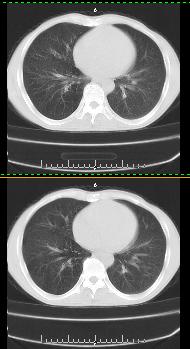

以下是引用liaoqiang在2008-3-21 17:45:00的发言:[br]右上叶尖段、后段有多发小结节和小条状影。考虑感染(结核可能性大。)。建议治疗后复查。

以下是引用王2008在2008-3-21 17:38:00的发言:[br]右上叶后段沿纹理走向呈串珠状.边缘欠清密度增高影,局部胸膜增厚.[br]考虑1.右上支扩可能.2.右上炎症.建议治疗后复查.请各位老师指教.

以下是引用lj11119999在2008-3-21 18:15:00的发言:[br]右上叶尖段、后段有多发小结节和小条状影。考虑感染(结核可能)建议进一步检查!